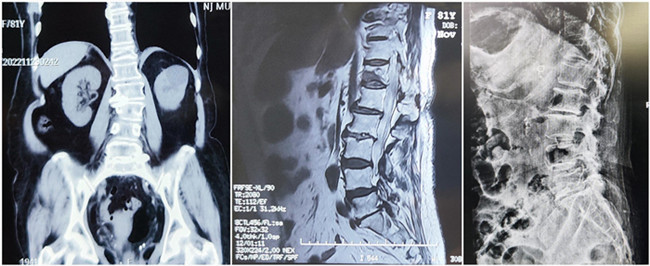

入院診斷:胸椎壓縮性骨折(T12)(主診斷);腰椎滑脫;腦梗死;高血壓1級;糖尿病。

*患者術(shù)前影像